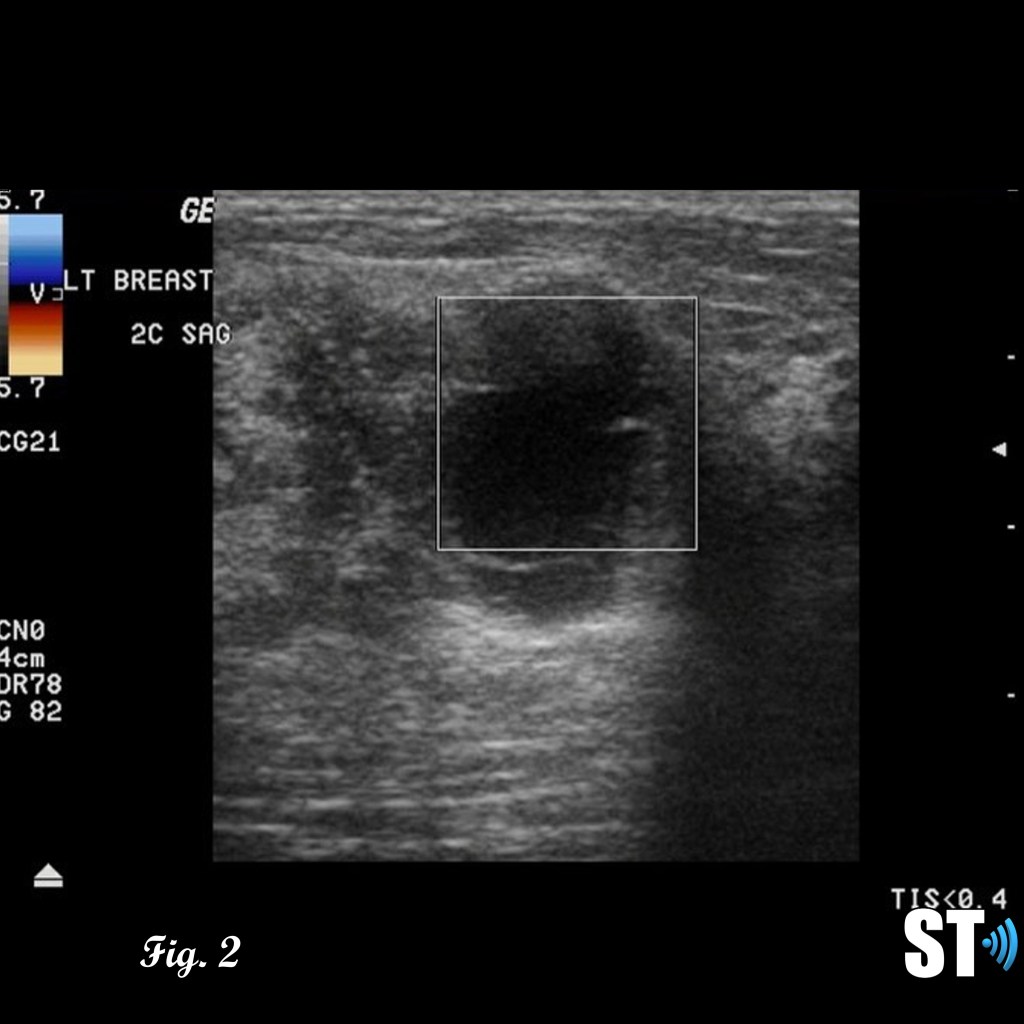

Ultrasound

Patients with suspicious or palpable masses are often referred to ultrasound for further evaluation. Phyllodes tumors can exhibit characteristics similar to fibroadenomas such as; hypoechoic, well demarcated, solid. Features like rapid growth, large size at presentation and cystic areas can raise suspicion for phyllodes.

Fig. 1-3 17 yo Female with complex cystic/solid breast lesion that resulted to be phyllodes.